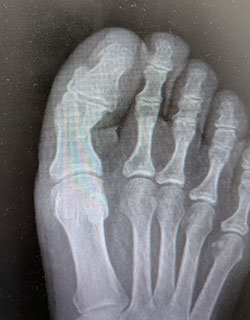

Displaced fracture of the great toe, before and after anatomic reduction using absorbable fixation pin (skin staples are in place and are removed at three weeks).

Before SurgeryBefore

After SurgeryAfter